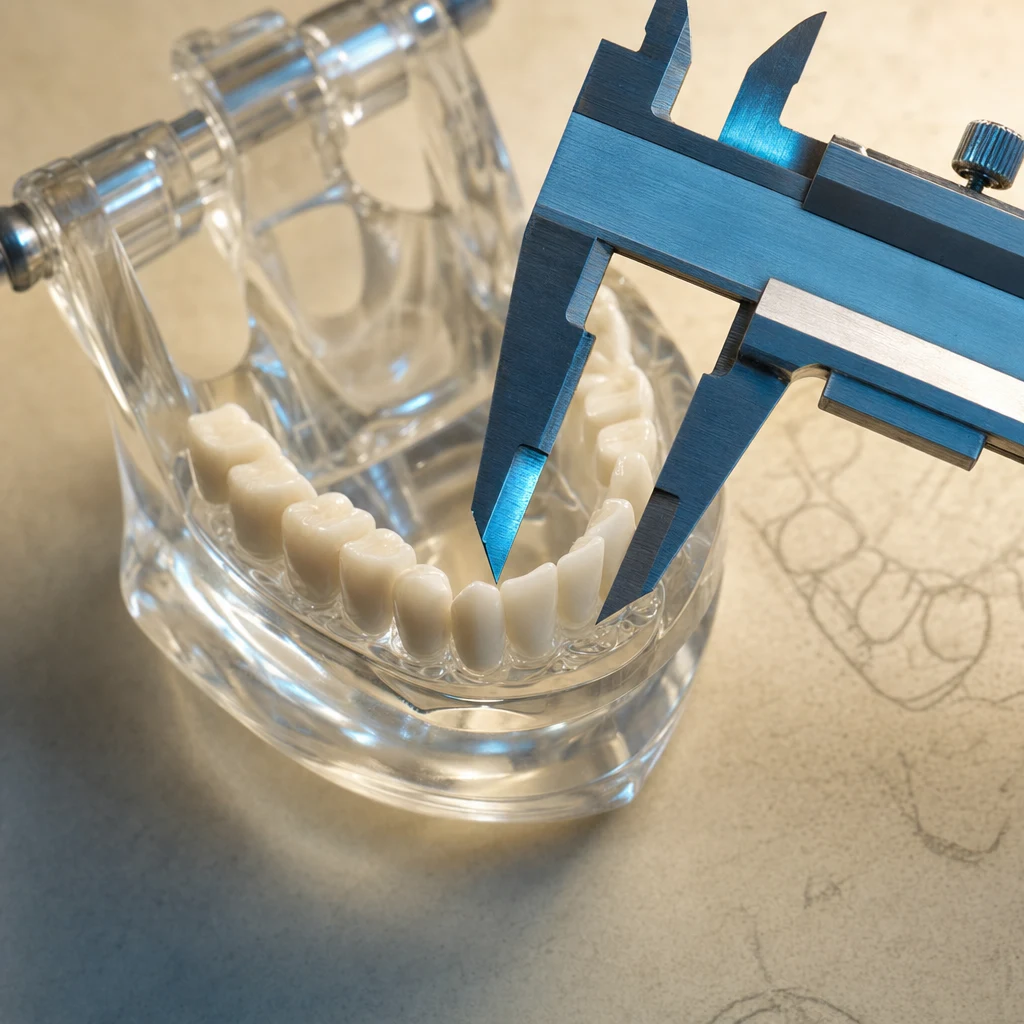

2단계 — 3D CT 촬영

임플란트는 잇몸뼈 안으로 들어가는 시술이라 2D X-ray만으로는 부족합니다. CT로 다음을 확인합니다:

- 잇몸뼈의 폭·높이·밀도

- 신경관(하악신경, 상악동) 위치

- 골이식 필요 여부 판단

CT 결과를 바탕으로 식립 위치·각도·픽스처 종류·골이식 필요성·예상 기간·총비용을 정합니다. 케이스에 따라 모형을 제작해 시술 시뮬레이션을 보여드리는 경우도 있습니다.